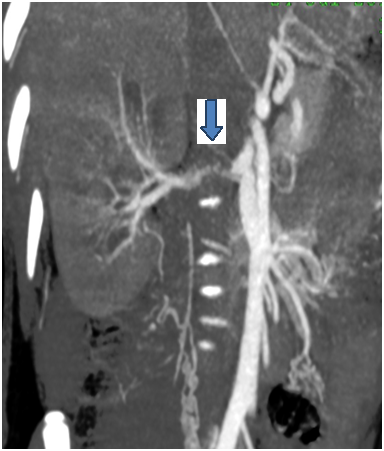

A 19 years old male patient, who was suffering from severe hypertension which was not controlled despite 5 antihypertensive drugs. Routine investigations revealed high serum creatinine 7.3mg/dl, serum K; 2.8meq/L with normal other lab results. The patient urine output was approximately 1000 ml per day. On examination, blood pressure was 240/110, bilateral midzonal and basal crepitation of chest, mild bilateral lower limb edema, and respiratory rate was 32/minute and hypoxia (So2 was 85 %) were reported. Therefore, the patient received oxygen support and hemodialysis (HD) session with ultra filtration of 4 liters on a provisional diagnosis of pulmonary edema with improvement of the patient. Renal ultrasound revealed small sized atrophic pyelonephritic left kidney and the right kidney size was 12.5*4 cm with normal sonoghraphic appearance. Renal Doppler showed absent diastole in most of waves of the right renal vessels, resistive index (RI) of right main renal artery was 0.82 with peak systolic velocity (PSV) 22 cm/s and RI of right intrarenal artery was 0.87 with PSV 12.7cm/s. Right renal artery stenosis was diagnosed and confirmed by computed tomography angiogram (CTA) which detected single right renal artery with narrowing of its caliber at the proximal part (16 mm) (Figure 1). Renogram had shown severe parenchymal tracer (MAG3) retention in the affected right kidney mostly due to renal artery stenosis and non-functioning left one. Thus, right renal angioplasty with stenting was decided. But, the procedure complicated with broken guide catheter tip (about 3 cm lengths) and the distal part was impacted in the renal artery and the proximal part in the aorta (Figure 2). Consequently, immediate abdominal exploration was done for removal of the broken part. The surgery passed smoothly and the patient referred to ICU with stable hemodynamics. The patient maintained on HD and hypertensive drugs for 3 weeks then the patient underwent a successful right renal angioplasty with two stents fixation (Figure 3).The blood pressure and serum creatinine started to improve, HD was stopped and the patient was discharged after 2 weeks with serum creatinine 0.9mg/dl, four antihypertensive drugs, warfarin and aspirin with cessation of warfarin six months later. Currently, the patient has maintained on 2 antihypertensive drugs, aspirin with stable kidney function and controlled blood pressure.

Figure 1 Computed tomography angiogram of renal artery demonstrates single right renal artery with narrowing of its caliber at the proximal part (the arrow)